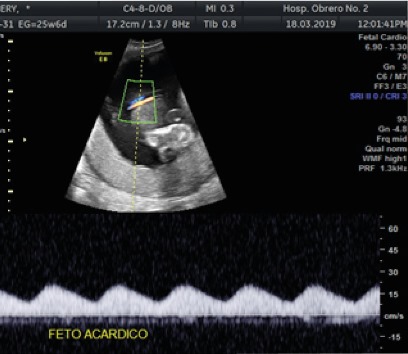

El estudio morfológico realizado a las 19 semanas, en servicio particular, ya concluía como: embarazo gemelar monocorial biamniótico con un feto normal y el otro acárdico. Con este resultado acudió al servicio de Ginecología y obstetricia del Hospital Obrero No 2 de donde fue referido a la Unidad de Medicina fetal al que acudió recién en la semana 21. En esta unidad, se practicó un nuevo estudio ecográfico encontrándose los siguientes hallazgos: secuencia TRAP en gestación gemelar monocorial biamniótico con un feto vivo normal (feto bomba) sin afectación hemodinámica y el otro feto acárdico ( figura 1).

Para la semana 30 la paciente empezó con contracciones uterinas, modificaciones cervicales y acortamiento del cuello; el peso estimado fetal para ese momento fue de 1817 gramos, sin signos de falla de bomba, un líquido amniótico normal; el feto acárdico presento un volumen aproximado de 2569cc. Se programó cesárea de urgencia con el diagnóstico de Embarazo de 30,5 semanas, Secuencia TRAP en embarazo gemelar monocorial biamniótico con un feto vivo y otro acárdico, inicio de trabajo de parto. Con la cesárea se obtuvo un feto vivo de sexo femenino normal de 1700 gramos de peso y el gemelo acárdico amorfo de 2300 gramos, ambos pesos dentro del rango de peso calculado por ecografía. ( Figura 2).